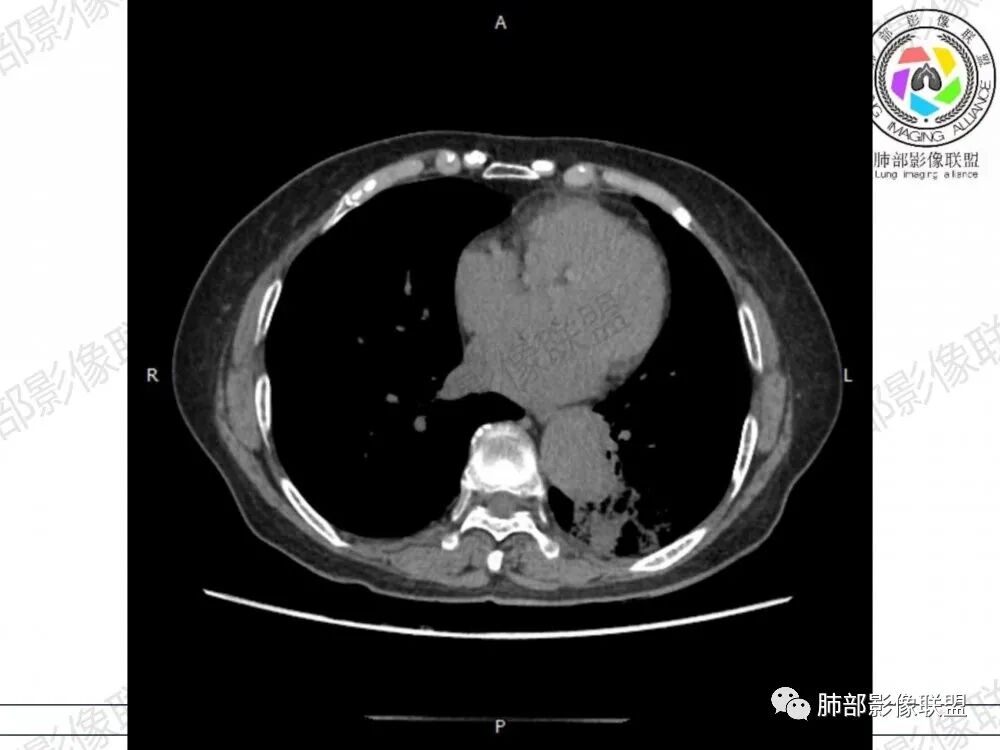

晨读病例,老年人男性 左肺下叶病灶,实性病变加上边界清晰的磨玻璃影,实性病变可见明显的膨胀性生长,增强实性部分可见血管照影征,考虑腺癌,粘液腺癌可能。

左肺下叶实变及磨玻璃影,宽基底与胸膜相远,磨玻璃边界清晰,边缘膨隆,病变内近端支气管堵塞,不均匀强化,可见血管影,考虑腺癌,鉴别结核

胸CT:左下叶胸膜下大片斑片影,长轴沿胸膜分布,实变、GGO混杂,磨玻璃边界清晰,粘液密度,小叶内间隔增厚,支气管进入后堵塞(枯枝),增强轻中度强化,血管造影征。常规考虑:肺腺癌?淋巴瘤?鉴别不典型病原体感染。

2、影像表现:无肺气肿背景,病变定位于左肺下叶背内侧基底段,病灶呈不规则团块影,靠近胸膜侧,其内密度不均匀,内见空洞、实变及磨玻璃影,磨玻璃影呈碎石路征,边界清楚,实性肿块边界膨隆,其内见空洞。空洞周围比较实。病灶较大的支气管通畅,细小的支气管成“枯枝征”。无胸膜增厚及胸膜腔积液,增强扫描呈中度强化,见血管造影征。

2、典型的粘液腺癌,收缩力很弱,肺泡壁断裂常有,张力存在,早期较少出现张力表现,破坏力偏弱,支气管与肺血管大多保留,所以增强病灶内见强化血管影(血池),也是粘液腺癌另一个特点。